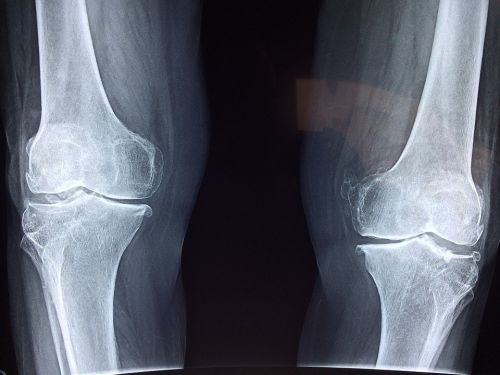

Причина № 1. Гонартроз коленного сустава

Гонартроз – с таким диагнозом люди сталкиваются чаще всего, когда у них болит коленный сустав (это около 35 % случаев). В данном случае происходит дегенерация хряща. Заболевание развивается медленно, но прогрессирует неуклонно, в итоге приводя к полному разрушению сустава.